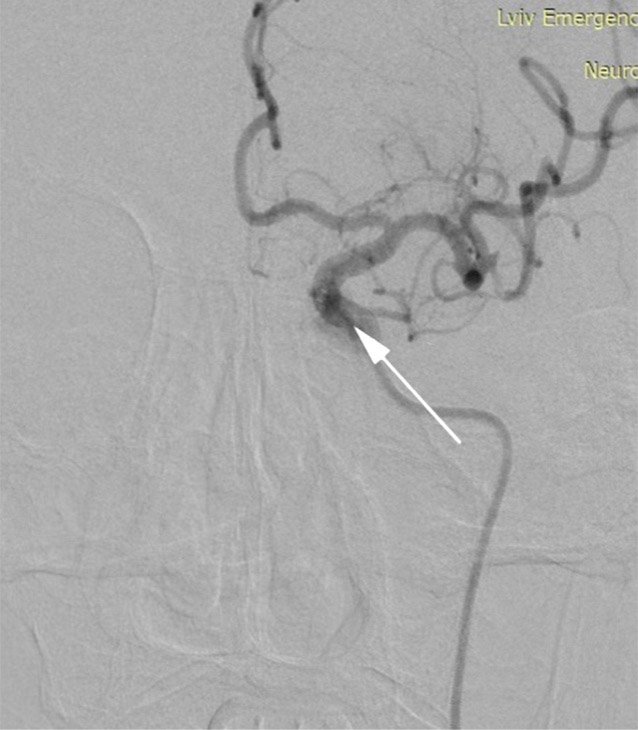

Invasive AP monitoring was performed under fluoroscopic guidance in the extracranial segment of the main artery (C1 segment of the ICA) using a standard aspiration catheter (length – 132 cm; inner diameter – 1.80 mm) and in the MCA distal to the thrombus using a standard microcatheter (length – 153 cm; inner diameter – 0.81 mm) prior to the deployment of a stent retriever. The results were recorded using an HP Engage Flex Pro portable computer (HP Inc., USA) connected to a compatible pressure transducer (part of the Philips Azurion 7 angiographic hemodynamic monitoring system; Philips Medical Systems Nederland B.V., Best, Netherlands). After calibration, the transducer was connected via a fluid-filled line to the catheter cannula. Calibration of the sensor was performed before each measurement (Fig. 2).

A B

Fig. 2. Invasive AP waveform recording: A – distal to the thrombus in the middle cerebral artery (MCA); B – proximal to the thrombus in the internal carotid artery (ICA)